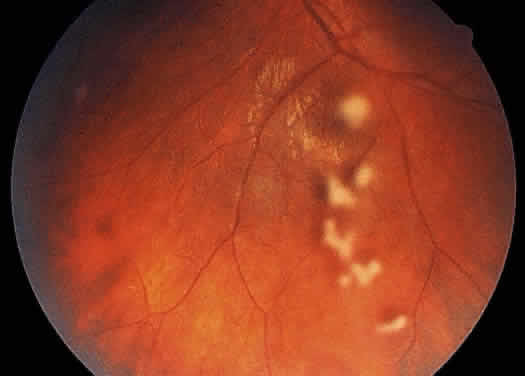

The retinal vessels should be examined for evidence of vasculitis, noting whether the vasculitis affects primarily the veins (phlebitis) or the arteries (arteritis). Patients with sarcoid uveitis commonly have extensive periphlebitis, whereas patients with Behçet's disease may have more of an arteritic picture. Patients with herpetic retinitis may have extensive arteritis and phlebitis, which produce the appearance of “frosted branch angiitis”37 (Fig. 13).